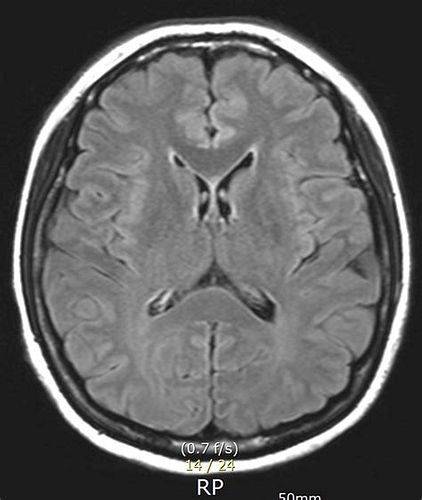

뇌 MRI (자기공명영상) 검사

뇌 MRA (뇌혈관 자기공명영상) 검사

MRI와 MRA 검사 비용

MRI(자기공명영상)와 MRA(자기공명혈관조영술) 검사의 비용은 병원, 장비, 검사 범위, 조영제 사용 여부,

건강보험 적용 여부 등에 따라 달라집니다.

아래는 2024~2025년 기준 국내 주요 병원 및 실제 사례를 바탕으로 정리한 평균 비용입니다.

MRI 검사 비용

MRA 검사 비용